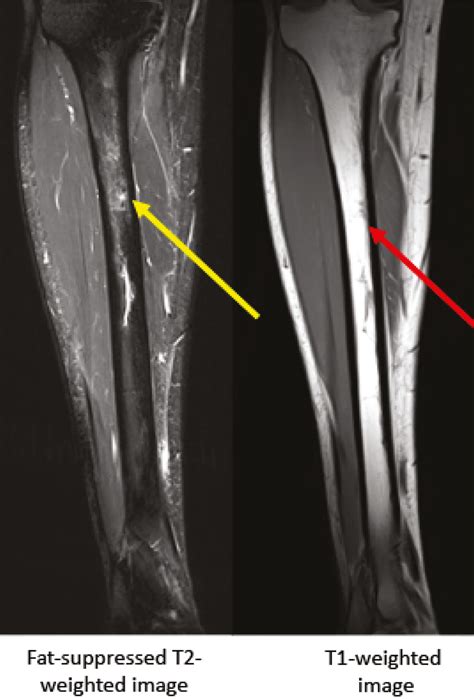

Doctors may suggest more sensitive imaging techniques if clinical symptoms remain high despite a clear X-ray. An MRI is often considered the "gold standard" for diagnosing a stress fracture tibia because it can detect bone marrow edema (swelling inside the bone), which is an early sign of stress-related injury before a fracture line even forms.